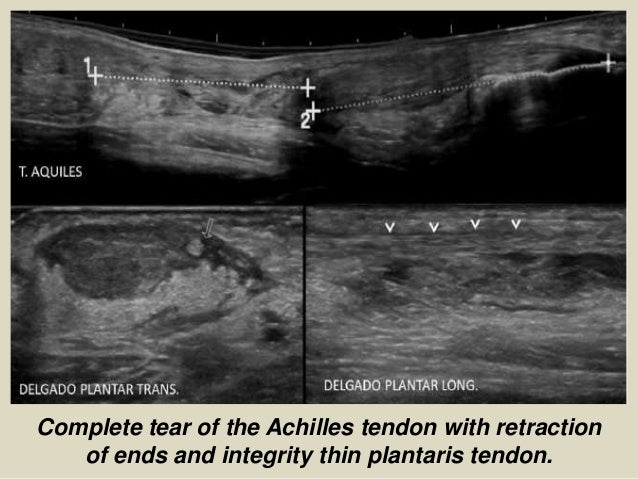

Complete tear of the Achilles tendon with retraction

of ends and integrity thin plantaris tendon.

25. 25. Complete tear of the Achilles tendon with retraction of ends and integrity thin plantaris tendon.